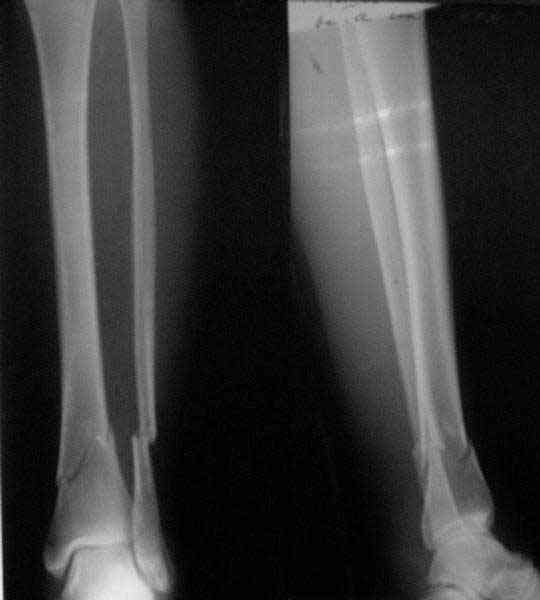

A typical case is attached, also an image with intra-op reduction obtained by a small wire distractor, in the moment of insertion a Poller wire in AP direction. Fixation by a SIGN nail. Despite the fibula was not fixed healing was obtained with the unchanged alignment.

Very interesting application, but is the final position in a little distal varus with some fibula

distraction? Would that have been eliminated by fibula plating?

TDVC> Very interesting application, but is the final position in a

TDVC> little distal varus with some fibula distraction?

At least both the ankle mortise and tibial alignment look acceptable, don't they?

TDVC> Would that have been eliminated by fibula plating?

I am just trying to illustrate that prevention of 1)tibial valgus and 2)loss of reduction can be provided without fibular plating. Small changes of conventional nailing techniques allow to maintain reduction of the tibia reliably without adjunctive fibular stabilization.